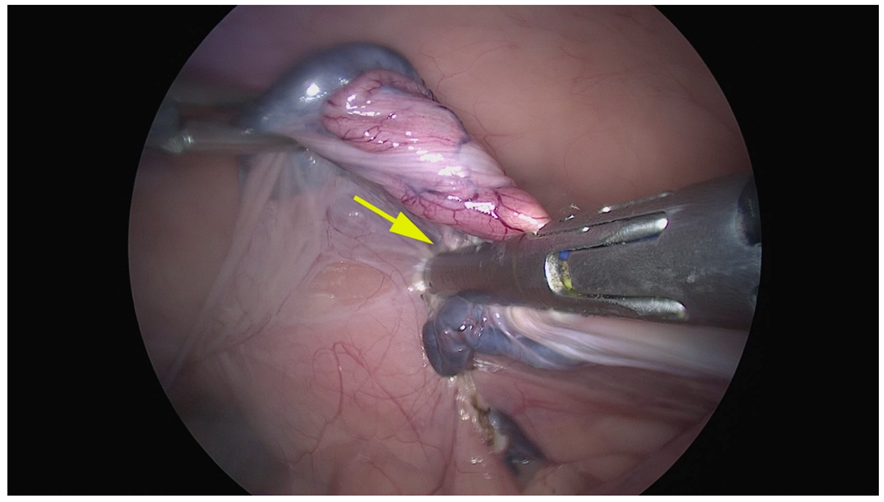

Figure 3.

Representative image of the right ovariectomy performed by Atlas. Cranial is on the left. Yellow arrow shows that the branches clamped incompletely the cranial tip of the uterus incompletely, requiring several applications to be completed.

In the Atlas group, we noticed a grade 1 bleeding score in one case and grade 2 hemorrhage from the cranial uterine horn in two cases, which necessitated several coagulations and bleeding monitoring. However, the bleeding was successfully managed and did not necessitate conversion. In the Caiman group, no bleeding was observed (median score = 0 ± s. e. 0, range 0), and the median bleeding score in the Atlas group was 0.5 ± s. e. 0.4; range 0–2). However, this difference was not statistically significant (p > 0.05) (Figure 4).

Figure 4.

Representative image of right ovariectomy performed by the Caiman 12. The yellow arrow shows that the entire tissue was completely included between the branches.